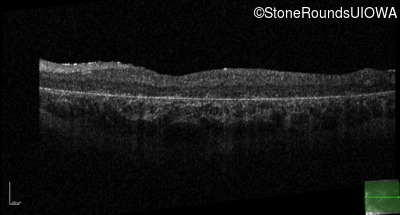

Optical Coherence Tomography - Left - 5/200

Exemplar / OCT Stack